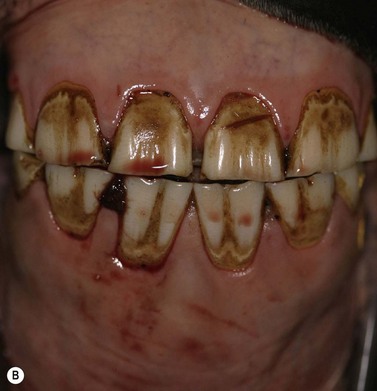

Clinical features

SSC tumors are characteristically slow growing but occasionally have a more rapid course. They can be proliferative at least initially, but usually become very destructive, ulcerative and infiltrate widely into local tissues of the mouth including the lips, buccal mucosa, hard palate and tongue.48 Early lesions may simply resemble a non-healing wound but more advanced, destructive carcinoma lesions have a characteristic foul odour.

Metastases to local lymph nodes can occur, although the general sentiment is that they do not do so commonly.49 In theory, they may disseminate to the lungs and elsewhere. However, this behavior is rare in oral forms of SCC.50

Oral SCC may involve the lips (Fig.11.13A), hard palate51 (Figs 11.13B,C), tongue51,52 (Figs 11.13D,E) or oral mucosa (Fig. 11.13F). It is also quite common for oral SCC to invade the nasal cavity and the paranasal sinuses (often to the point of gross distortion or obstruction to airflow).53 Some SCCs involve the base of the tongue (Fig. 11.13E) and pharynx (Fig. 11.13G) and can physically affect their function. Where the nasal cavity and paranasal sinuses are involved, there may be altered airflow (or even complete obstruction of the ipsilateral nostril). Horses with pharyngeal and lingual SCCs may present with dysphagia of progressive, insidious onset. In all cases, weight loss and poor general health are common.

Fig. 11.13 (A) A destructive carcinoma on the lip of a 23-year-old pony gelding. Note the extensive tissue destruction and the loss of the maxillary teeth. Treatment with intralesional cisplatin and topical 5-fluorouracil was not effective. (B) Facial distortion due to nasopalatine squamous cell carcinoma in a 12-year-old pony gelding. (C) A histologic section of the endonasal carcinoma shown in (B). Solid cords of squamous carcinoma are surrounded by fibrous stroma and trabeculae of non-neoplastic reactive bone (arrows). (D) Squamous cell carcinoma of the pharynx, which was identified some 3 months after a lesion had been detected in the hard palate. It is possible that this developed independently or that it was an extension of the earlier lesion. (E) Carcinoma of the free portion of the tongue. The local lymph node was enlarged (see J); slide courtesy of Dr R.R. Pascoe. (F) This highly destructive oral carcinoma developed in a 4-year-old Warmblood. It involved the maxillary bone and resulted in dental problems also.

(G) This horse was presented with weight loss and dysphagia. The highly destructive oral and invasive carcinoma was not visible endoscopically from the pharynx and was only seen with difficulty during an oral examination. (H) Photomicrograph of cords of solid squamous cell carcinoma with deep invasion of the tongue. (I) Metastasis of squamous cell carcinoma to regional lymph node showing cords of tumor cells (arrows) beneath cortical lymphoid tissue.

More extensive spread may involve the orbit and the cranial cavity with secondary involvement, respectively, of the eye or even rostral brain when the cribriform plate is eroded by tumor. It is also quite common for nasal SCC to invade the hard palate, forming an oronasal fistula. In all cases, there may be extensive soft-tissue disruption and consequent loosening/shedding of the teeth.

The location of SCC means that tumors are frequently detected late when a large invasive mass may already be present projecting from the gum or hard palate as a grayish, ulcerated and bleeding mass. Where the tumor surrounds a tooth, this may become dislodged, and in almost all cases there is a fetid odor from the mouth. Involvement of the lips and gums is usually clinically obvious; early tumors are often identified incidentally during routine dental procedures.

Diagnostic confirmation

Biopsy is characteristic (Figs 11.13H,I). The pathologist should try to classify the degree of differentiation of the cells; highly differentiated carcinomas are far less dangerous than the undifferentiated ones. Biopsy sites should be carefully chosen to reflect the main carcinoma, with inclusion of a marginal zone as well. Punch or wedge biopsy sites should not be scrubbed or even washed before collection, and the biopsy site should not be sutured afterwards since wound dehiscence is almost certain. Fine needle aspirates and impression smears can be used but may be misleading, since they often consist mainly of stroma and inflammatory cells.

Pathology

Histologically, the tumor has distinctive characteristics with irregular cords of downward-invading neoplastic keratinocytes. (Figs 11.13H,I). A SCC characteristically has large amounts of non-neoplastic fibrous stroma in which inflammatory cells are plentiful. The abundant stroma results in a lesion that is characteristically tough or scirrhous when palpated or excised. The accumulation of variable amounts of keratin produces ‘keratin pearls’ in well differentiated tumors that can be used to define the likely malignancy of the lesion. Poorly differentiated carcinoma shows a more anaplastic cell structure, higher rates of division (high mitotic index), and much less keratin and, therefore, can closely resemble aggressive myxosarcoma. SCC is one of the better defined equine oral neoplasms.